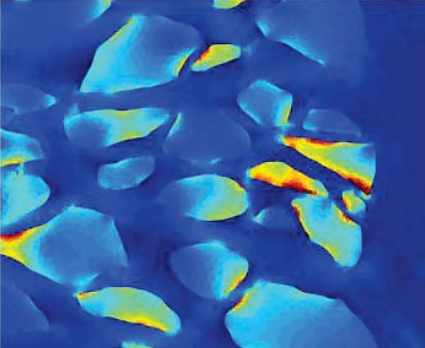

• Test-retest reproducibility of atomic force microscopy measurements of human trabecular meshwork stiffness

• L Kagemann, J Candiello, G Wollstein, H Ishikawa, RA Bilonick, IA Sigal, C Jonescu-Cuypers, PN Kumta, JS Schuman

• Modeling and Artificial Intelligence in Ophthalmology, 2(4), 34-43, June 2020.